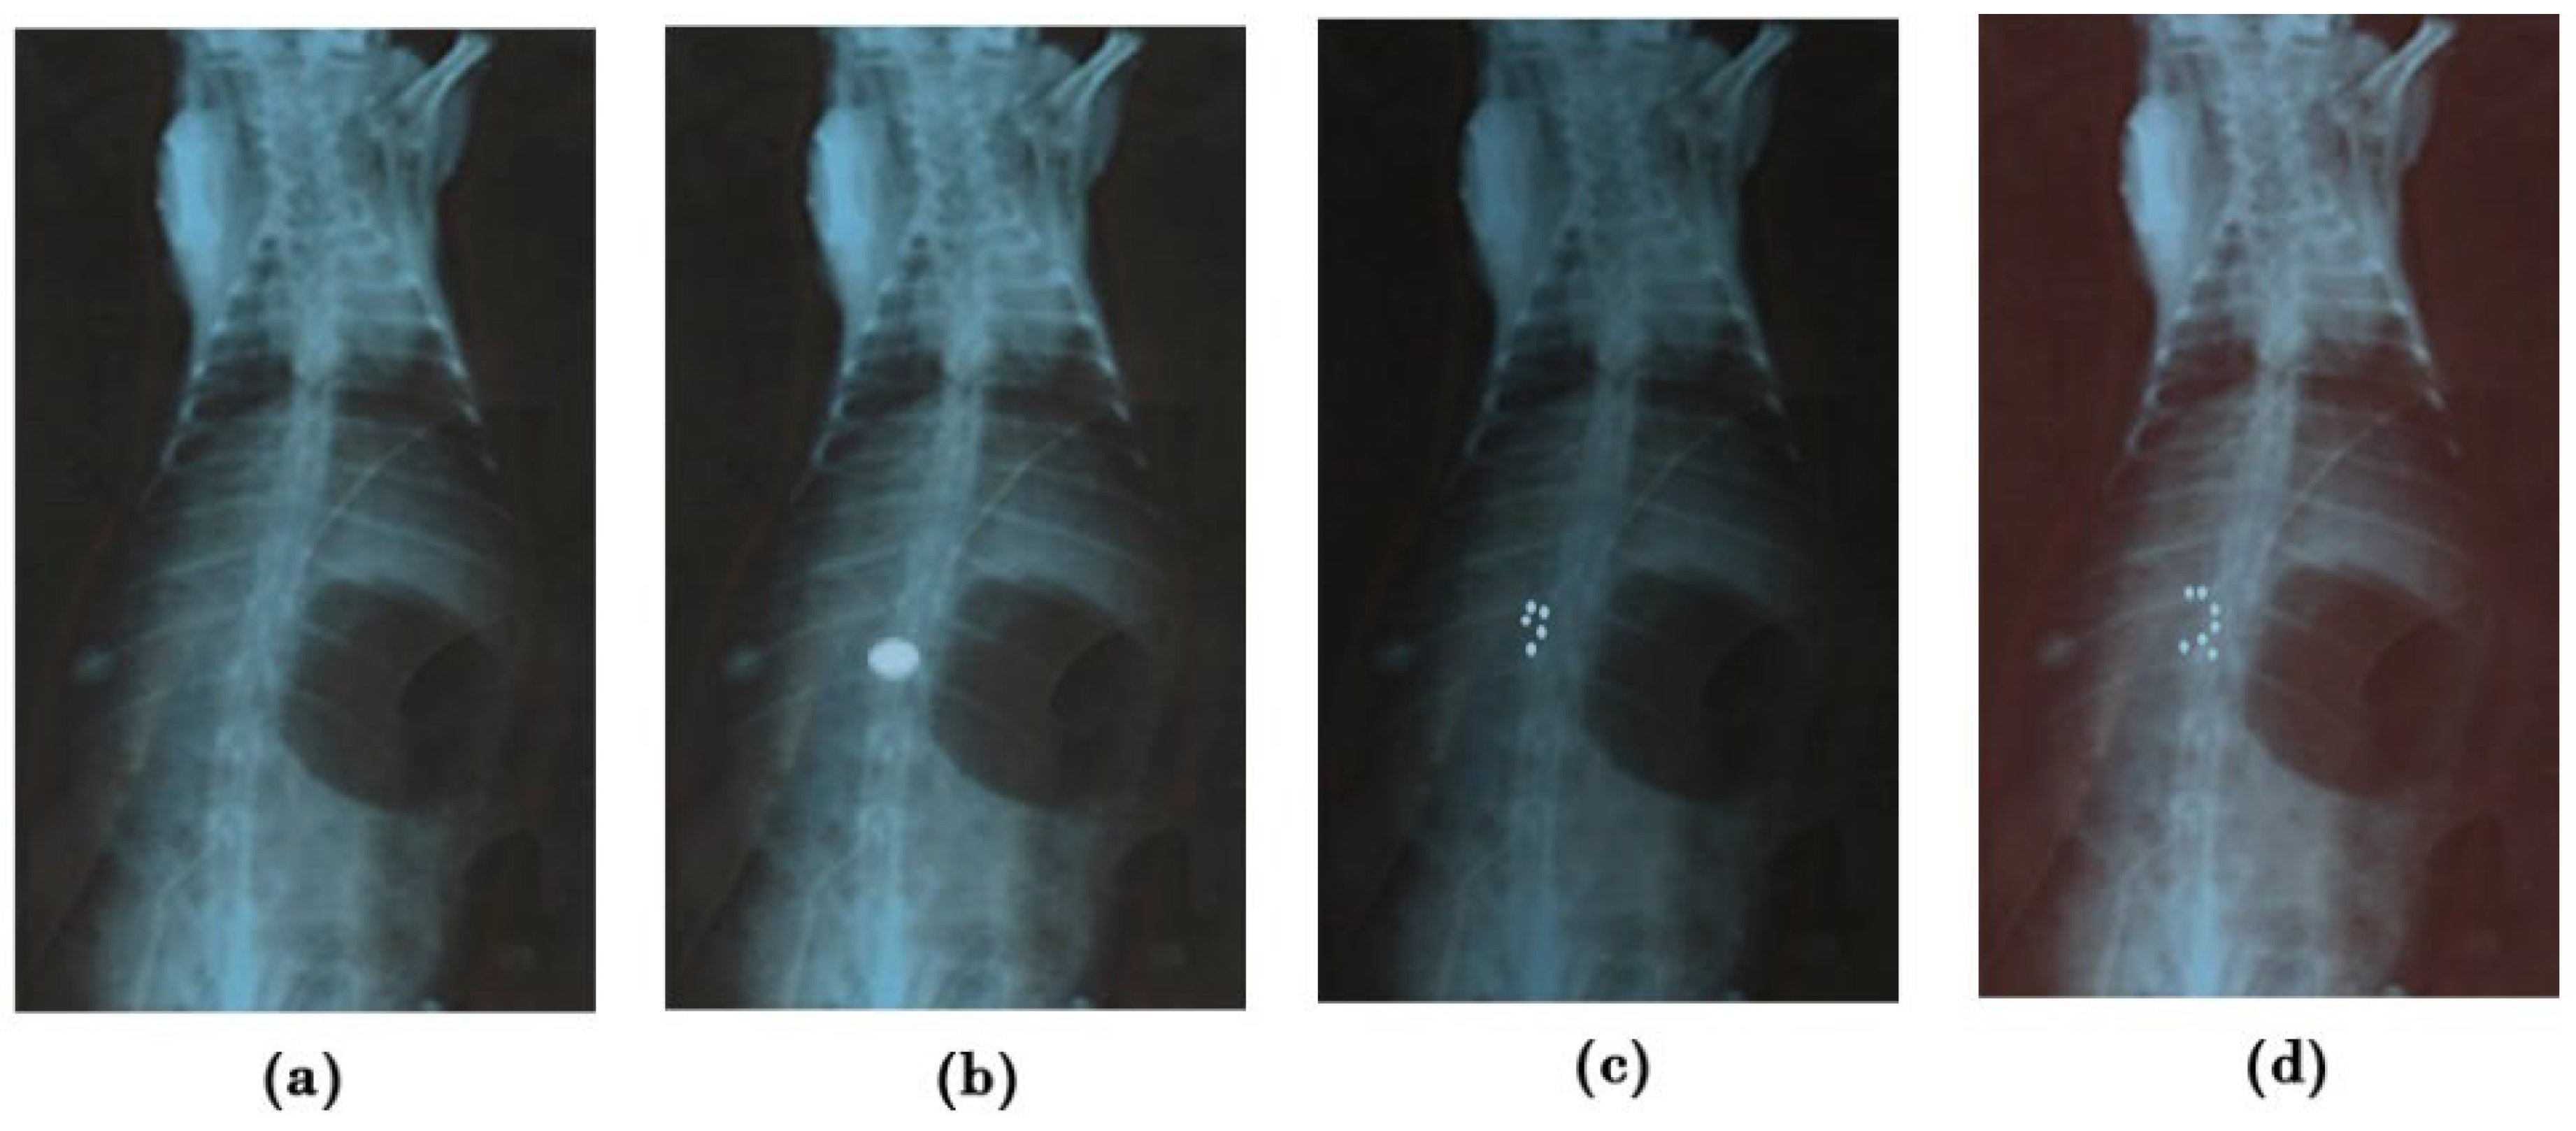

The X-ray method studied the mucoadherent behavior of G-STO-M in the rat stomach. Before administering a formulation, an X-ray photograph was taken (Figure 8a). Following 1 h post-administration, the next X-ray photographs were taken (Figure 8b). All the microspheres (500 mg)were found to accumulate in one region of the stomach and hence look like the impression of the tablet. The radiographic pictures attained at the end of 4 h disclosed that the group of microspheres was lightly changed in their position and segregated into five different groups, but the position was restricted to the mucosal region of the stomach. As the time extended, more groups of the formulation were evident. The formulation was capable of resisting peristaltic movements of the GIT even at the end of 8 h, as it established a secured disulfide bridge with the mucosa (Figure 8c,d).

Figure 8.

X-ray radiograms (a) before administering (b–d), showing mucoadhesion of G-STO-M at 1, 4, and 8 h, correspondingly.

The study was conducted with healthy albino rabbits of either sex bearing 2.5–3 kg of weight. The animals were subjected to 12 h of fasting and had access only to water throughout the study. A prior abdominal X-ray was done to confirm the absence of any radio-dense substances. Further, barium sulfate (15%) was integrated into the preparation (without the drug) to enable the microsphere’s visibility under X-ray. Around 500 mg of the formulation was ingested into the animal with a flexible tracheal tube together with 15 mL of water. Anesthesia was given to the animal, and abdominal X-ray scans were taken at distinct time intervals by positioning the animal in an upright posture with the assistance of a radiologist [36].